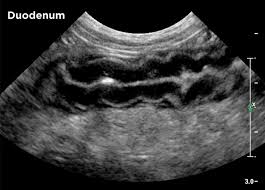

Signs Of Pancreatic Tumors In Dogs : Canine Insulinoma A Tumor In The Pancreas - You also may notice your dog hunching its back due to abdominal pain.. Pancreatic cancer in dogs can cause the pancreas to function intermittently, so that sometimes the symptoms may seem to have resolved, only to return again later. Some of the symptoms of this type of tumor include: Some animals may show signs of jaundice because a pancreatic tumor can obstruct the flow of bile from the liver to the small intestine resulting in elevated levels of bile products in the blood causing the skin and mucous membranes to appear yellow. It is the tumor of cells that line blood vessels, but most commonly affects heart, spleen, liver or skin. Experts aren't sure what causes the pancreas irritation, but some breeds, especially schnauzers, are more prone to it.

Abdominal pain cancerous growth in the pancreas is frequently very painful for your pet. Some animals show clinical signs suggestive of pancreatitis. In milder forms, symptoms aren't quite as obvious but may still include loss of appetite, lethargy, and diarrhoea. Some animals may show signs of jaundice because a pancreatic tumor can obstruct the flow of bile from the liver to the small intestine resulting in elevated levels of bile products in the blood causing the skin and mucous membranes to appear yellow. Pancreatic cancer in dogs can cause the pancreas to function intermittently, so that sometimes the symptoms may seem to have resolved, only to return again later.

Surgical treatment is significant for this disease. Symptoms of pancreatic cancer in dogs canine pancreatic cancer often doesn't cause symptoms until the disease reaches its later stages. Experts aren't sure what causes the pancreas irritation, but some breeds, especially schnauzers, are more prone to it. Because your dog cannot express his pain in words in the same way that a human can, you'll have to watch out for other signs that he is in pain. The warning signs of cancer in dogs are very similar to that in people. To spot signs of pancreatitis in dogs, keep an eye out for digestive distress, such as nausea, vomiting, and diarrhea. Read on and get more information on the symptoms, causes, and treatment of pancreatic cancer in dogs. Digestive problems digestive problems and issues with bowel movement are the most noticeable signs of potentially unhealthy pancreas. They may also show signs of abdominal pain and dehydration. An insulinoma is a tumor of the pancreas that affects the regulation of your dog's sugar levels, causing hypoglycemia, also referred to as low blood sugar. Less common causes are tumors that lead to obstruction of the pancreatic duct. Classic signs of pancreatitis in dogs. Abdominal pain cancerous growth in the pancreas is frequently very painful for your pet.